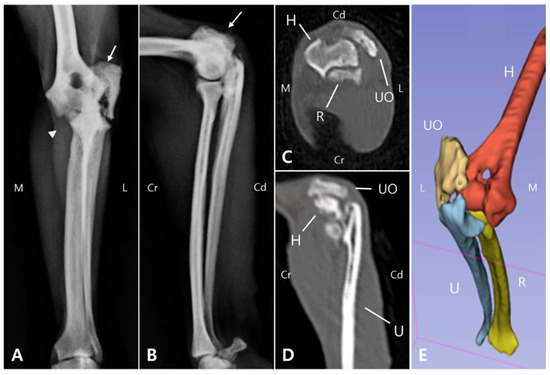

A six-year-old, neutered male Pomeranian weighing 4.25 kg was presented with a two-year history of non-weight-bearing lameness of the left thoracic limb following an untreated traumatic olecranon fracture. Orthopedic examination revealed markedly reduced elbow joint range of motion and muscle atrophy. Radiographs demonstrated [...] Read more.

A six-year-old, neutered male Pomeranian weighing 4.25 kg was presented with a two-year history of non-weight-bearing lameness of the left thoracic limb following an untreated traumatic olecranon fracture. Orthopedic examination revealed markedly reduced elbow joint range of motion and muscle atrophy. Radiographs demonstrated a distinct fracture line with proximolateral displacement of the olecranon fragment. Preoperative computed tomography (CT) and three-dimensional (3D) reconstruction were used to establish the surgical plan and to pre-contour a locking plate. Surgical treatment was performed in sequential steps, including removal of scar tissue, reopening of the bone marrow channel, and internal fixation. Considering the compromised biological environment of a chronic non-union, a bioactive graft composed of porous leaf-stacked structure (LSS) polycaprolactone particles incorporating recombinant human bone morphogenetic protein-2 (rhBMP-2) and mesenchymal stem cells (MSCs) was applied in combination with plate-screw fixation. The patient showed progressive improvement after surgery, achieving full weight-bearing and restoration of elbow joint motion comparable to the contralateral side. Follow-up radiographs and CT confirmed fracture union, and the radiolucency of the LSS scaffold enabled precise monitoring of bone healing. This case highlights the potential utility of combining patient-specific surgical planning with sustained delivery of rhBMP-2 and MSCs using LSS particles for the management of chronic non-union fractures in small animals. Full article

Figure 1